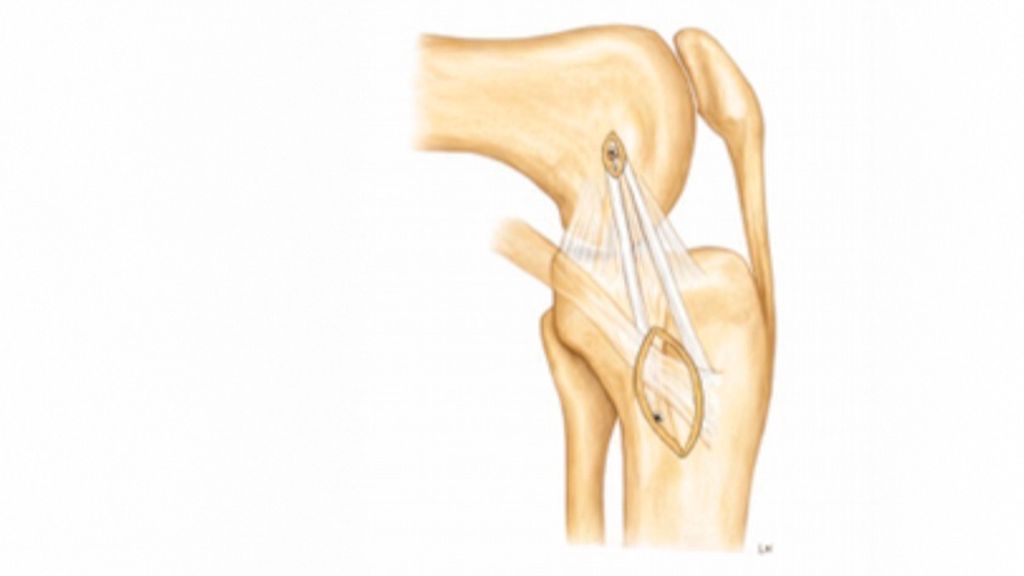

Anteromediale Tenodese

Die anteromediale Tenodese unter Verwendung der gestielten Gracilis- oder Semitendinosus-Sehne dient der Augmentation bzw. Rekonstruktion sowohl des tiefen als auch des oberflächlichen medialen Kollateralbandes (d/sMCL) über zwei funktionelle Bündel. Abhängig vom zugrunde liegenden Verletzungsmuster kann der Eingriff über einen minimalinvasiven oder einen offenen Zugang durchgeführt werden. Die Technik eignet sich bei akuten Eingriffen in Kombination mit einer MCL-Naht bzw. Refixation im Sinne eines „Bio-Brace“. Darüber hinaus kann sie bei chronischen Fällen mit leichter bis moderater anteromedialer Instabilität mit oder ohne VKB-Rekonstruktion durchgeführt werden. Der Ablauf eines solchen Eingriffes ist wie folgt: Die Sehne wird proximal mittels offenen Sehnenstrippers entnommen, während die tibiale Insertion erhalten bleibt. Die femorale Fixation der gedoppelten Sehne erfolgt im hinteren Anteil des nativen Ansatzes des oberflächlichen Längsbandes, während das freie Sehnenende im Zentrum der distalen tibialen Insertionsstelle des oberflächlichen medialen Kollateralbandes fixiert wird. Eine detaillierte Beschreibung der Operationstechnik ist über den QR-Code (Abb. 2,3) als Videoanleitung abrufbar.1